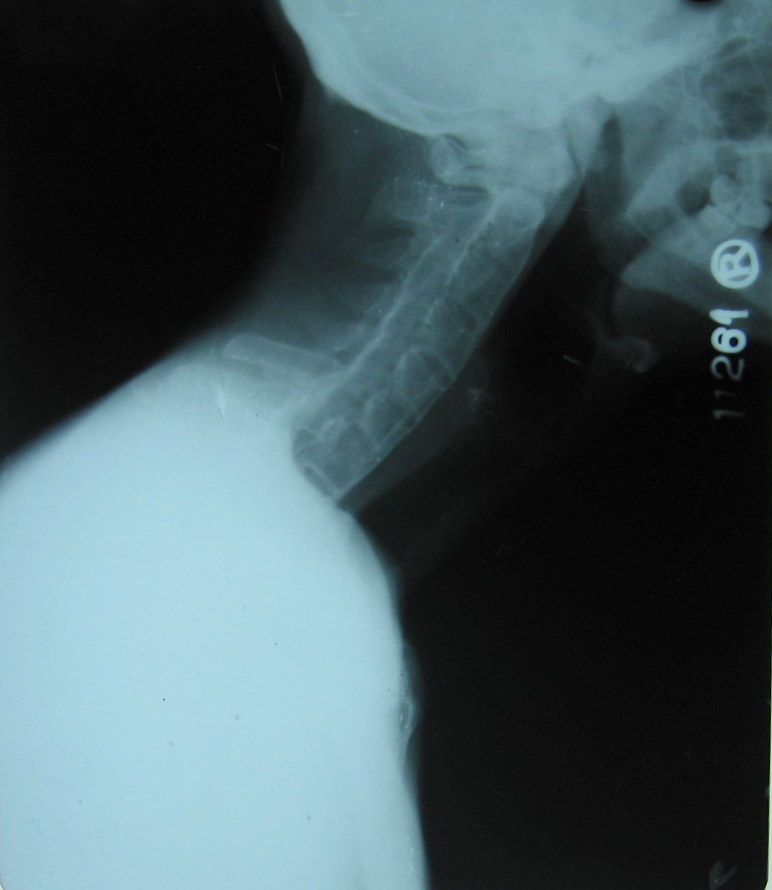

Neck Lateral – same patient